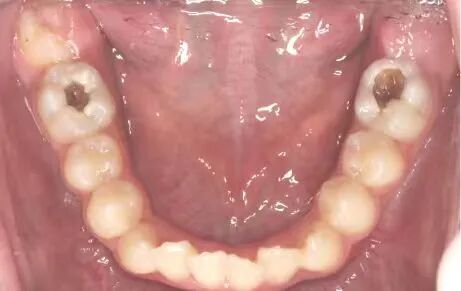

龋坏的牙齿↑ 河南省人民医院韩耀伦 供图